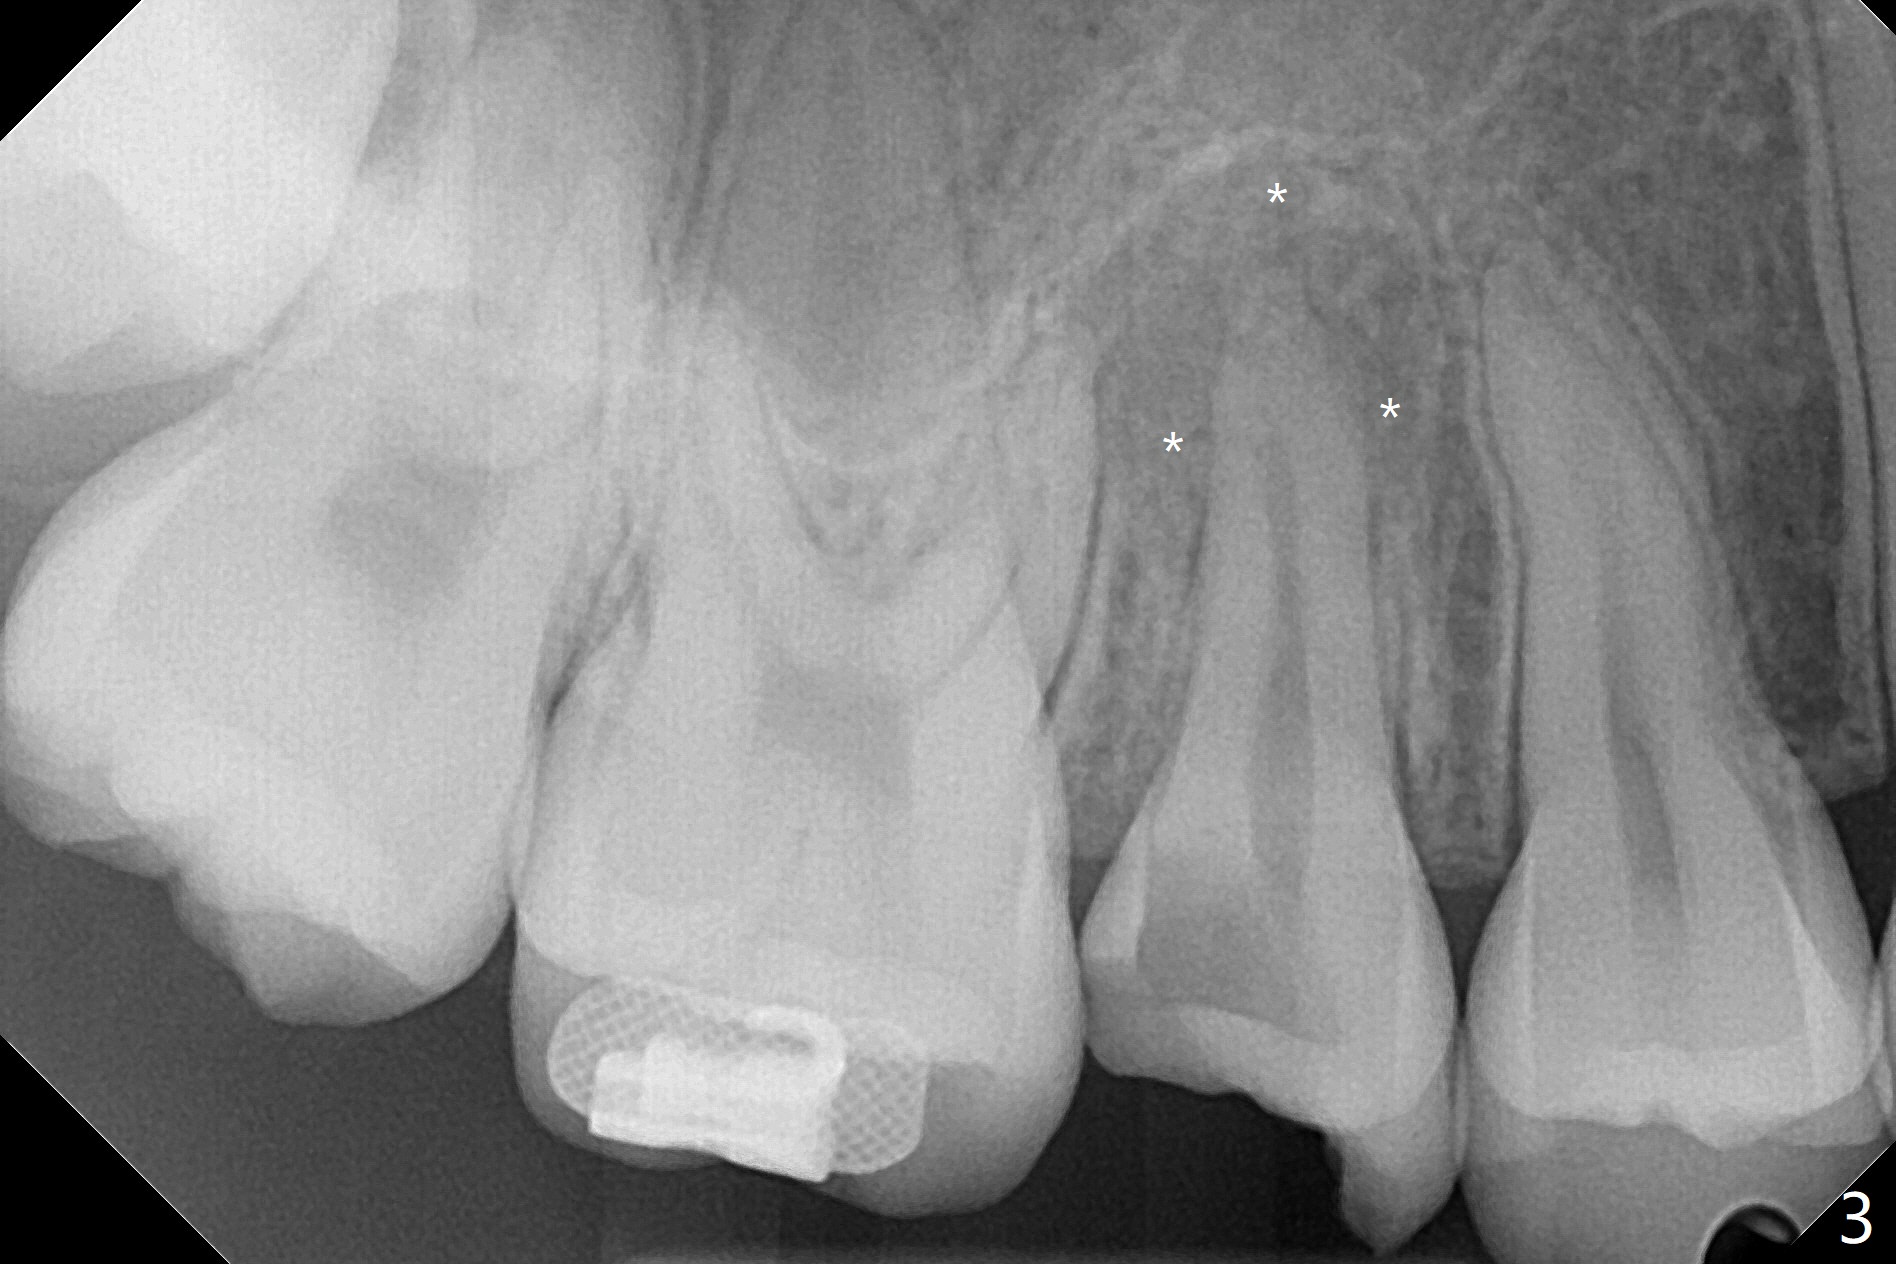

A 14-year-old woman with crowding returns to clinic for extraction of the 1st bicuspids. Orthodontic treatment has started partially. Because of severe caries at UR5 (Fig.1 *), BWs and PA are taken, which reveal DO incipient caries at UL, LL5 (Fig.2) and large PARL at UR5 (Fig.3 *). Upon receiving a revised treatment plan, four of 2nd bicuspids are extracted. The large PARL is confirmed intraop. Examination of the extracted teeth shows mesial caries at UL5, which is not detected by X-ray (Fig.4 <). By comparison, DL caries of UL5 is more severe (Fig.5). Check the neighboring teeth for caries when the patient returns for recall. The pulpal exposure of UR5 is large (Fig.6). So is the pulpal chamber (Fig.7). The large canal (Fig.7) in fact consists of 2 ones (Fig.11 red arrows) with a separation in between (*). The DL caries at LL5 is at the stage of decalcification (Fig.8), not visible in X-ray (Fig.12, as compared to Fig.7 >).